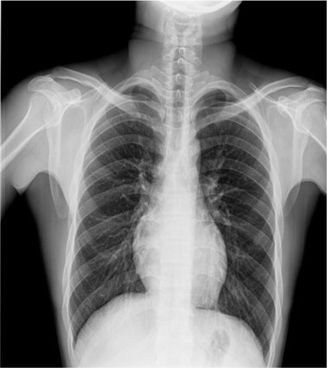

臨床圖片

微信圖片_20210927001119